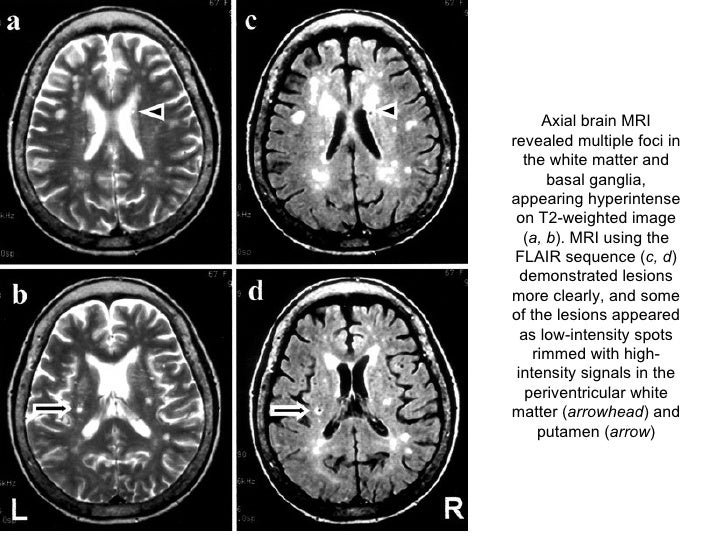

32+ White Spots On Brain Mri Migraine PNG. There are several causes of white spots on a brain mri, including small strokes, migraines, multiple sclerosis (ms), lupus, b12 deficiency, a brain. The white spots in the brain may indicate old age or areas which have been damaged.other tests may need to be done such as visual evoked potential i also have had bad headaches (migraines) and white spots were found on a ct scan and then later on a follow up mri.

Imaging Findings of Migraine

Imaging Findings of Migraine from img.medscapestatic.com

Sandra has since told daily mail australia that while 'some days are better than others' she is feeling a lot better and is regularly monitoring her health and checking in with. White spots on your mri. Mri can't diagnose migraines or headaches but it can rule out other medical conditions. Mri spots (white matter lesions) in patients with migraines.